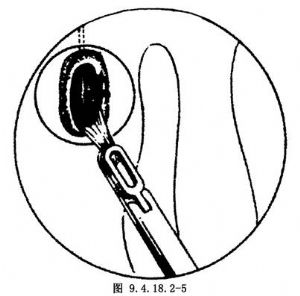

5.用镰状刀或剪刀切开泪囊壁(图9.4.18.2-4),可将骨窗相对应的泪囊壁切除(图9.4.18.2-5),或切成U形瓣翻相下或翻相后以覆盖相应的骨缘。